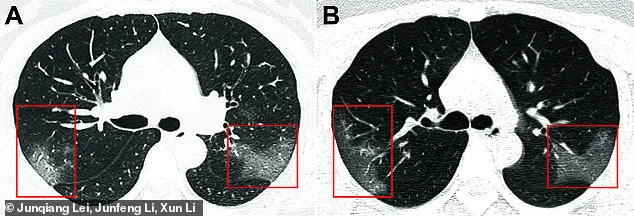

Ảnh chụp phổi của bệnh nhân nhiễm virus Corona tại Lan Châu. Phần đốm trắng thể hiện chất lỏng tích tụ trong phổi. Ảnh: DAILY MAIL

Hình ảnh cho thấy các mảng trắng ở góc dưới của phổi, lấp đầy một phần không gian dành cho không khí trong phổi.

Các mảng trắng xuất hiện rõ rệt hơn trong lần chụp X-quang thứ hai, được dán nhãn B, được thực hiện ba ngày sau lần đầu tiên và trong quá trình điều trị.

Ông Paras Lakhani, một bác sĩ chuyên về X-quang tại Đại học Thomas Jefferson (Mỹ), người không tham gia nghiên cứu nhưng có xem xét những hình ảnh trên, nhận xét: “Nếu bạn phóng to hình ảnh, chúng trông giống như những hạt thủy tinh mờ xếp chồng lên nhau. Trên thực tế, những gì chúng thể hiện là chất lỏng tích tụ trong không gian phổi”.